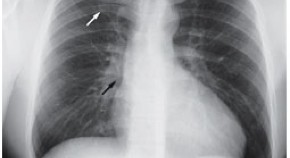

• Professor Stephen Westaby and colleagues describe the case of a patient who presented with cardiogenic shock that swiftly deteriorated to severe heart failure. CT revealed a large adrenal tumor that was subsequently indentified as pheochromocytoma. After the tumor was removed, the patient underwent left ventricular assist device implantation as a bridge to left ventricular recovery.